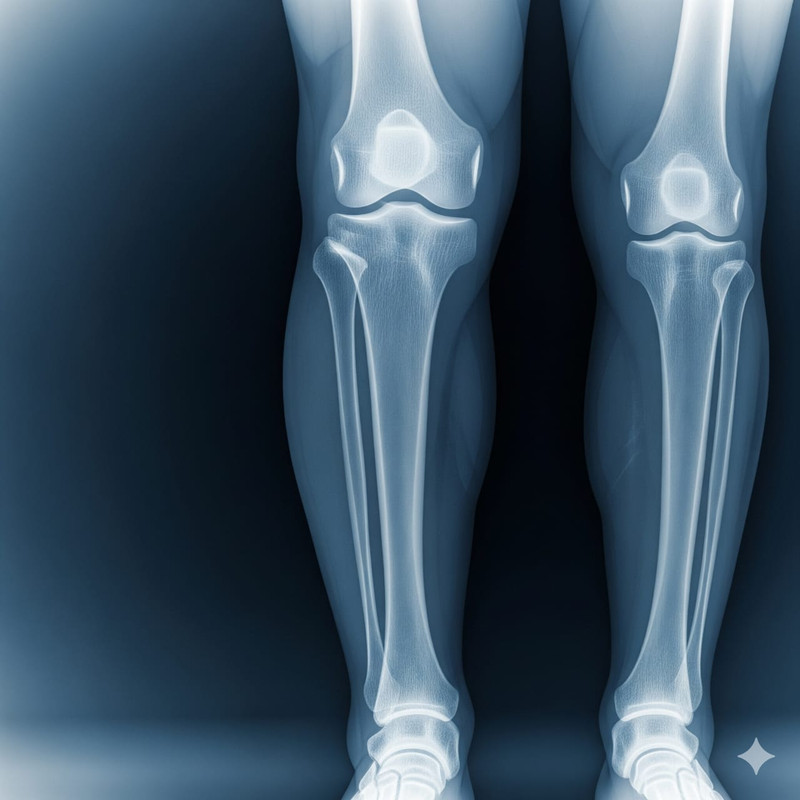

It is a traditional Ayurveda method, here we are fixing the bone fracture & paralysis patients’ treatment in the traditional way across our generations. At Maa Tara Seva Kendra we believe in healing the body naturally — through the power of Ayurveda, compassionate care, and traditional wisdom.

We also provide: Spondylitis (Kamar Dard), Arthritis (Ghutne ka Dard), Gastric problems, Gathia, Body pain massage, Piles, and handmade traditional medicines.